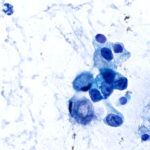

Consistent Results with ASP vial technology

Each FNA pass is placed into a propriety ASP vial and homogenized, ensuring the slide is always representative of the cell block. Control the volume of the sample for ROSE and preserve the rest for the cell block.